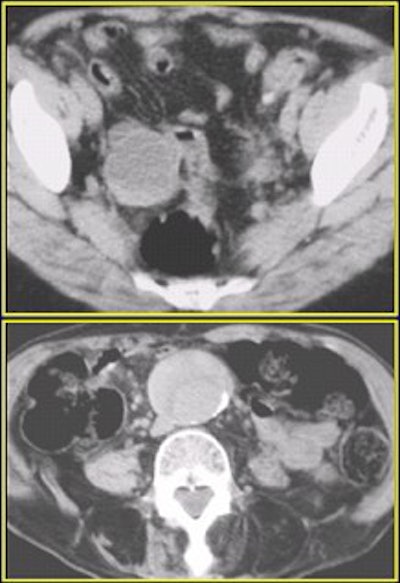

Left ureterovesicle junction stone (UVJ) as seen on the 120-mAs CT scan above and on the 240-mAs scan below.